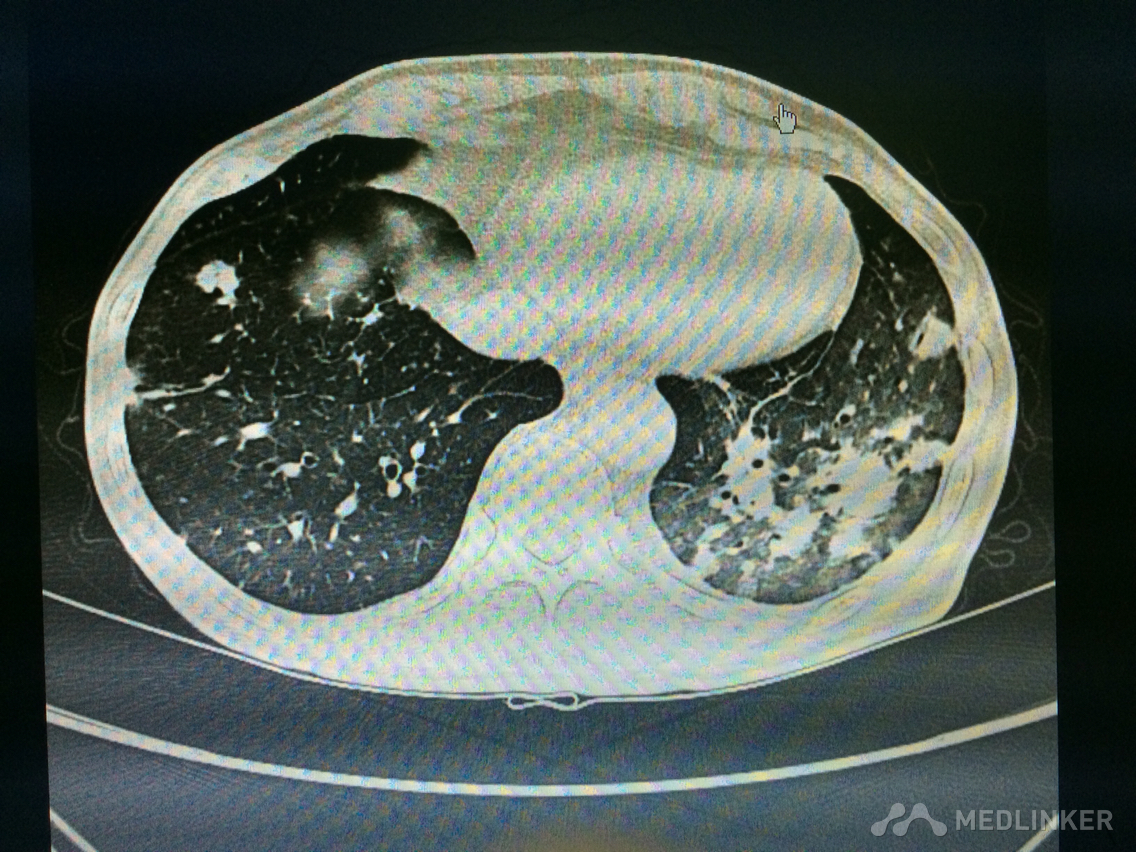

看这胸部CT?

咳嗽咳痰发热3天,伴胸痛气紧,偶痰中带血,体温38.7,伴全身乏力。

胸部!CT,,考虑什么?